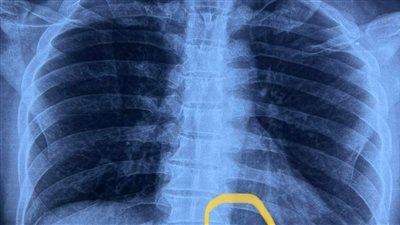

وكان فريق جراحي بمستشفى بنها الجامعي بمحافظة القليوبية بقيادة الدكتور محمد أحمد الجزار استشاري جراحة القلب والصدر بمستشفى بنها الجامعي قد نجح فى استخراج إبرة تنجيد دخلت عن طريق الخطأ فى ظهر مريض خلف القفص الصدري مباشرةوالتى ظلت بمكانها مدة عامين حيث جري إجراء جراحة بفتح جراحي صغير 3 سم، استخراج إبرة تنجيد دخلت بطريق الخطأ فى ظهر مريض خلف القفص الصدرى مباشرة حيث تركها المريض لمدة سنتين خوفا من إجراء العملي.

ووفق بيان المستشفي فقد جري حجز المريض بالقسم وتجهيزه لعملية سريعة، تم فيها الاستعانة بجهاز الأشعة الملحق بغرف العمليات (C-arm)، حيث تم تحديد مكان الإبرة والفتح الجراحي عليها مباشرة، واستخراجها بنجاح،ولكن علي هيئة قطع منكسرة بسبب الصدأ، نظرا لبقائها طوال هذه المدة.

وأضاف الجزار ان خطورة وصعوبة الجراحة في هذه الحالة تمثلت في وجود الابرة في الظهر مما يستدعي قلب المريض علي بطنه بعد تخديره وهو امر صعب وخطير وطبيا والصعوبة الثانية في عدم معرفة مكان الابرة بالضبط في الجسم مما تتطلب إستخدام جهاز اشعه داخل غرفة العمليات مما سهل تحديد المكان وإستخراجها علي هيئة قطع بسبب تعرضها للصدأ.